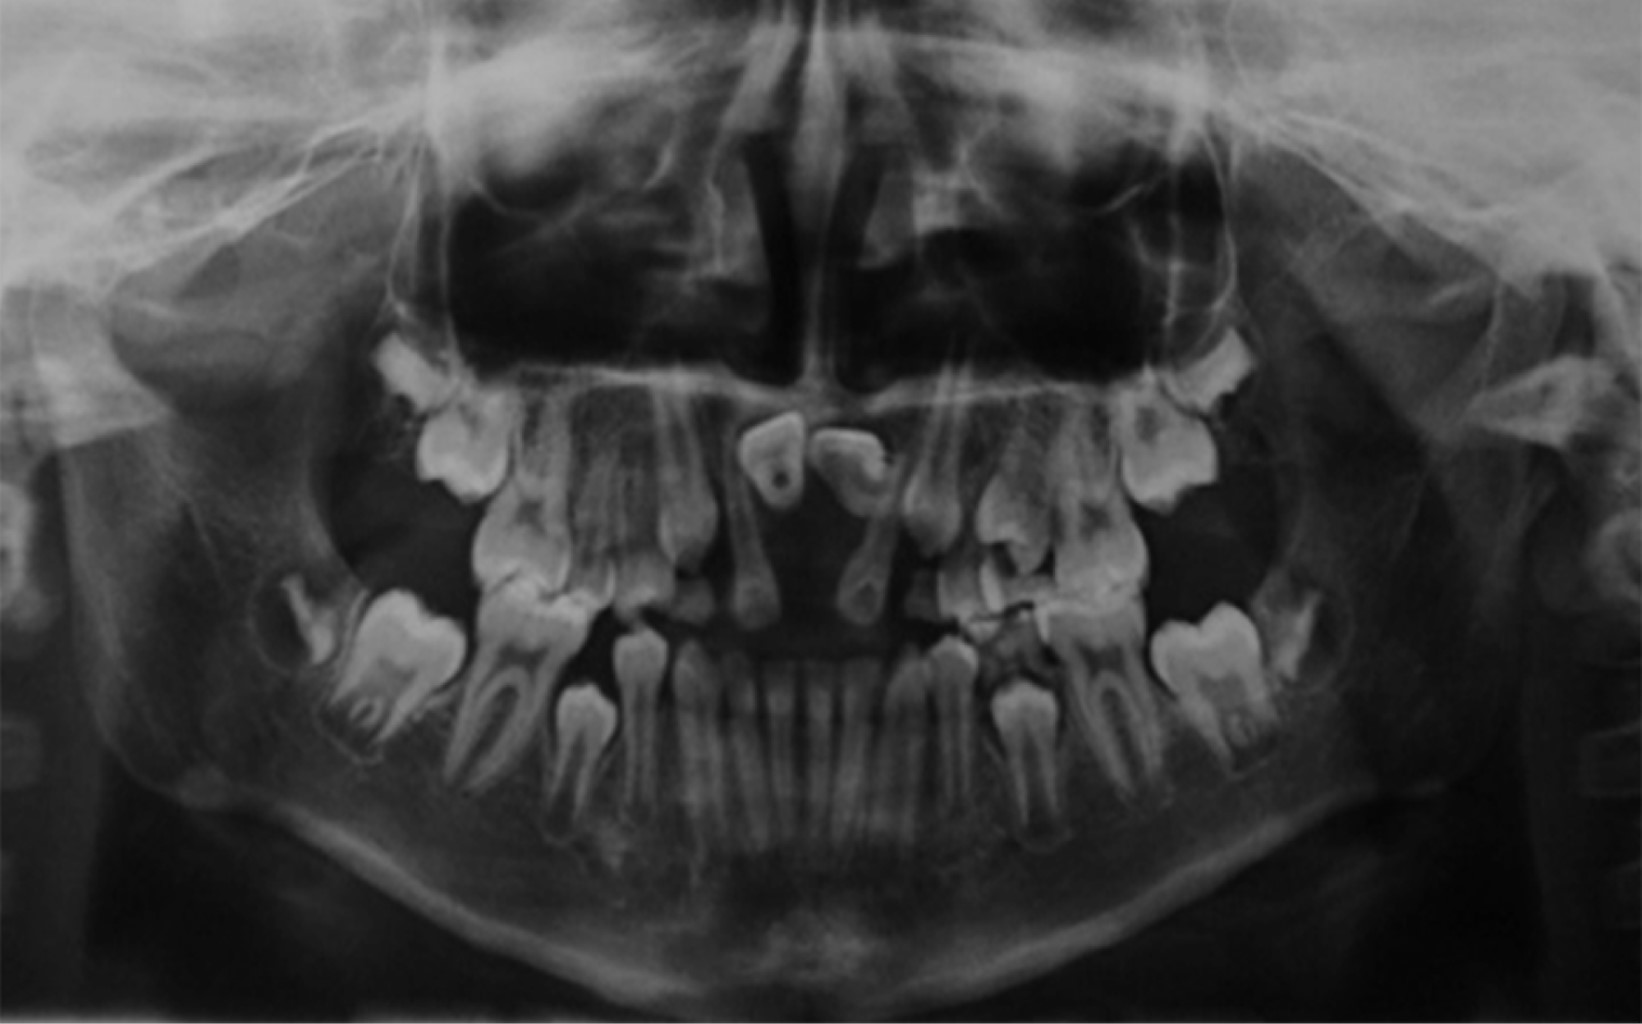

A 12-year-old male patient, with sequelae of secondary palate, presents at the Centro de Alta Especialidad "Dr. Rafael Lucio" with the consultation reason "my front teeth are missing", no allergies or habits; mesofacial biotype, oval face, symmetrical, mid-facial line with non-assessable teeth; dental organs #11 and #21 retained in horizontal position at apical level; openbite and anterior crossbite; bilateral class I molar; bilateral non-assessable canine class.

According to the extraoral and intraoral photographs (Figures 1 and 2), radiographic studies (Figures 3 and 4), and cephalometric data (Table 1), orthodontic treatment with traction of dental organs #11 and #21 was decided in order to fulfil the planned objectives. The treatment was carried out in three phases.

The duration of treatment was 48 months, the position of dental organs #11 and #21 was adequate, the overbite was corrected, bilateral class I canine and class I molar were achieved, a positive arch smile, correct anterior guidance (overjet and overbite), coincidence of midlines, elimination of open bite in the anterior sector (Figures 5 and 6); the correct position of the dental organs #11 and #21 was observed in the radiographic examination, with no root resorption and, bone neoformation adjacent to the traction site (Figure 7).